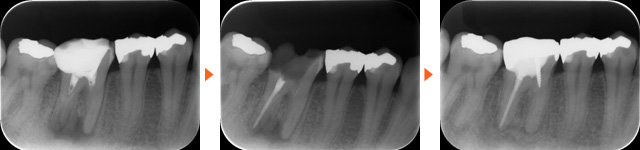

根管治療は、歯の内部にある神経や血管が細菌に感染した際に行う処置です。むし歯が神経まで進んでしまった場合や、外傷によって歯の根が折れたりヒビが入ったりした際に適応されます。

治療では、まず感染した神経を取り除き、根管と呼ばれる細い管の中を丁寧に形成・洗浄・消毒します。根管は非常に細く暗い上に複雑な形をしているため、繊細で時間のかかる処置が必要になります。そのため、治療が一度で終わることは少なく、複数回の通院が必要になる場合があります。

根管治療は、神経まで細菌が到達した重度のむし歯に対して行う処置で、歯を抜かずに残すための「最後の砦」といえる治療です。もし根管治療を行わなければ、感染はさらに広がり、抜歯を避けることができなくなります。

この治療を適切に行うことで、むし歯による激しい痛みから解放され、さらに失われた歯の形を修復することも可能になります。治療後は歯の土台を整え、クラウンなどの被せ物を装着することで、機能性と見た目の両面を回復させることができます。

歯科用CTは、歯や顎の内部を三次元で撮影できる装置です。根管は非常に細く複雑な形をしており、歯によっては複数に枝分かれしています。従来の平面的なレントゲンでは確認が難しかった部分も、CTによる立体画像なら鮮明に把握できます。

これにより、根管の構造や感染部位の位置・大きさを正確に診断できるため、治療の精度が格段に向上します。